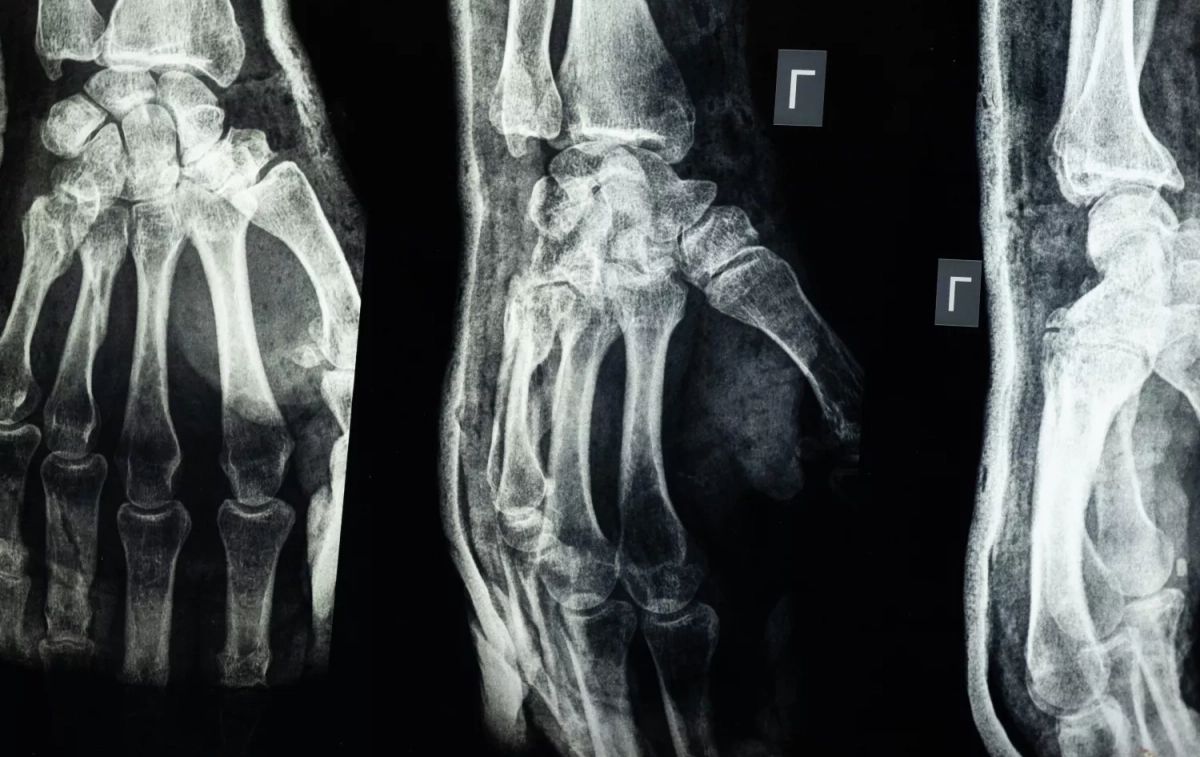

“En el caso de la osteoporosis senil los síntomas pueden ser la pérdida de altura, un aumento de la curvatura de la espalda que produce una cifosis y, si ésta es muy pronunciada, puede crear dificultades al caminar”, expone Alegre de Miquel. “Las fracturas más comunes son la de la muñeca (fractura de Colles), las de las vértebras y las de cuello de fémur”, especifica.